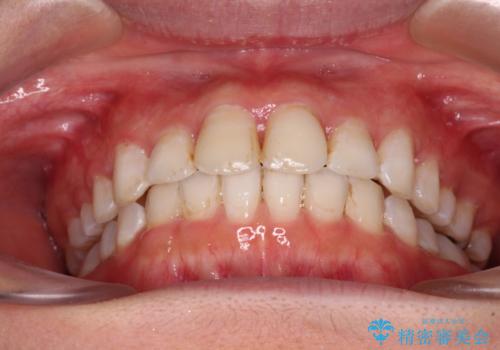

前歯の捻れを改善 インビザラインによる矯正治療

- 前歯の翼状捻転を気にして来院された患者様です。

全体的に叢生は軽度であったため、インビザラインにて矯正治療を行うこととしました。

前歯の幅の大きさも気になっていたため、IPRにより叢生を解消するとともに、歯の大きさも改善しました。